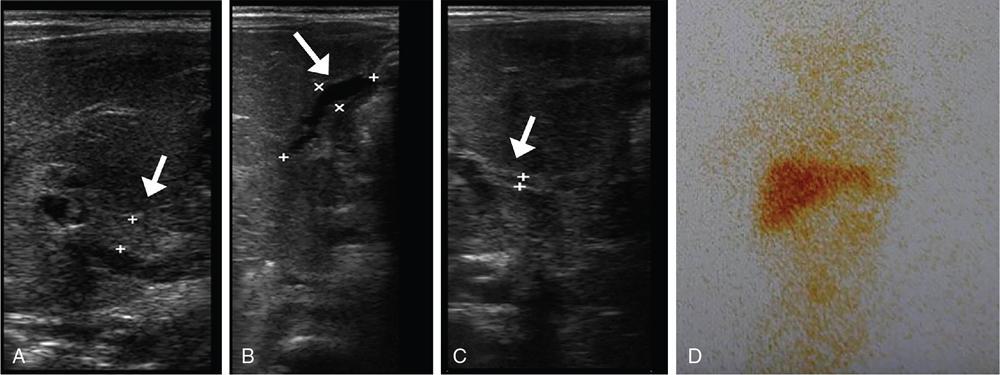

Subramaniyan Ramanathan, Vineetha Raghu, Tahiya Salem Alyafei, Mahmoud Al Heidous Congenital hepatobiliary anomalies include a variety of conditions often presenting with neonatal jaundice early in life or portal hypertension later in life, and some of them can be asymptomatic and incidentally discovered in adults. They may be due to several hereditary or developmental disorders. Physiological jaundice in the neonatal period typically occurs at 3–7 days, and bilirubin levels are <12 mg/dL in full term and <14 mg/dL in preterm neonates. The onset of jaundice before 24 hours, the presence of jaundice persisting beyond 2 weeks, exceeding the normal range, or the presence of conjugated hyperbilirubinemia are abnormal. In this chapter, we discuss in detail the various imaging features with a brief note on the clinical presentation, pathogenesis and management of biliary atresia, Alagille syndrome, Caroli’s disease, choledochal cysts, congenital hepatic fibrosis, polycystic liver disease and biliary hamartoma. Biliary atresia results from severe to complete obliteration of the extrahepatic biliary tree, and accounts for one-third of the cases of persistent neonatal jaundice. Its incidence varies from 1:10,000 to 1:25,000 births with higher rates among Asian population. The possible aetiopathogenesis of this condition is thought to be perinatal foetal cholangitis with or without a malformed biliary tree. The two most common causes of neonatal cholestasis include biliary atresia and neonatal hepatitis, and they together encompass 60%–90% of cases. Although the clinical and biochemical features are very similar in these two conditions, their management is different and imaging plays a central role in differentiating these closely related conditions. Prompt diagnosis and urgent surgical management may help prevent cirrhosis and permanent liver damage. This is owing to the fact that small patent biliary ductules are present at the hepatic hilum at birth which gradually fibrose and disappear by 3–4 months. This condition is associated with situs inversus; congenital heart disease; trisomies 17, 18, 21 and choledochal cysts. Polysplenia is the most common extrahepatic anomaly associated with biliary atresia described as biliary atresia splenic malformation (BASM) and found in 20% of the patients. Clinically, the child presents with signs of obstructive jaundice, including yellowish discolouration of skin and mucosa, dark urine and pale stools. Hepatomegaly may be present. Cirrhosis and portal hypertension may develop if untreated. Laboratory investigations reveal conjugated hyperbilirubinemia, elevated alkaline phosphatase, gamma-glutamyl transpeptidase and serum aminotransferases. Biliary atresia can be categorized into three types based on the extent of biliary involvement, known as the Kasai classification (Table 9.7.1) US is the first screening test and is usually requested to distinguish biliary atresia from neonatal hepatitis. Various findings have been described and can be categorized into primary and secondary features. Primary features include triangular cord sign, abnormal gallbladder, poor postprandial contractility and absent common bile duct (CBD). Hepatomegaly, splenomegaly and enlarged right hepatic artery are the secondary findings. The triangular cord sign has been described as a triangle-shaped or tubular echogenic structure measuring more than 3 mm seen anterior to the portal vein; this sign, although highly specific, has a low sensitivity. The gallbladder ‘ghost triad’ has been described in biliary atresia as gallbladder with length less than 1.9 cm, indistinct wall with lack of complete echogenic mucosal lining and irregularity of its outline. The Lee criterion refers to the thickness of anterior wall of the right portal vein measuring more than 4 mm. Other findings include enlarged hepatic artery >1.5 mm and ratio of hepatic artery to portal vein diameter >0.45. Overall, triangular cord sign shows the highest diagnostic accuracy with a reported sensitivity of 74% and specificity of 97%. The combination of gallbladder abnormalities and triangular cord sign can be used to increase the sensitivity to 95% (Fig. 9.7.1). Hepatobiliary scintigraphy (Hepatobiliary iminodiacetic acid or HIDA, 99mtechnetium mebrofenin, diisopropyl-iminodiacetic acid or the DISIDA scan), endoscopic retrograde cholangiopancreatography (ERCP) and intraoperative cholangiography are further investigations which aid in the diagnosis. The HIDA scan reveals liver uptake with biliary nonexcretion of the radioisotope into the bowel at 24 hours, and has a sensitivity approaching 100%. However, it has a lesser specificity of 75%–80%. Severe hepatocellular dysfunction may also lead to nonexcretion of tracer into the gut and may confound the diagnosis. Magnetic resonance cholangiopancreatography (MRCP) can be used to demonstrate the intrahepatic ducts and CBD in equivocal cases, thereby ruling out biliary atresia. However, it is a technically difficult examination to perform in neonates due to the need for sedation, cost and availability issues. Although both false positives and false negatives have been reported, limited available studies show good diagnostic accuracy with one recent study reporting approximate sensitivity of 97% and specificity of 95% for the MRI triangular cord sign. If the diagnosis could not be reached on imaging, liver biopsy can be useful in a certain subset of patients. Last resort for definitive diagnosis is intraoperative cholangiogram and it remains the gold standard. Portoenterostomy (Kasai procedure) is the surgical treatment of choice; however, it is unlikely to be of value if performed after the child is 3 months old. Later in the course of the disease, hepatic transplantation is the treatment of choice. Alagille syndrome is a rare hereditary condition characterized by chronic cholestasis and has an autosomal dominant transmission with variable penetration. However, about 50% of the cases are sporadic, occurring due to de novo mutations involving the JAG1 or NOTCH2 gene. It is an important cause of familial neonatal cholestasis with an incidence of 1 per 100,000 live births. In contrast to biliary atresia which predominantly involves the extrahepatic biliary tree, there is hypoplasia/paucity of the interlobular biliary ducts (PIBD). It may also present with abnormal facies, ocular abnormalities, hepatosplenomegaly, vertebral anomalies, peripheral pulmonary stenosis and cardiac malformations. Approximately 15% of these patients go on to develop cirrhosis and liver failure. Intracranial haemorrhage and moyamoya-like condition resulting from associated vascular anomalies may account for a significant percentage of mortality and morbidity. Differential diagnoses include biliary atresia, neonatal hepatitis and progressive familial intrahepatic cholestasis (Byler’s disease). Other disorders causing bile duct paucity include alpha-1-antitrypsin deficiency, cystic fibrosis and Zellweger syndrome amongst others. Imaging features depend on disease severity and include hepatomegaly, periportal fibrosis/cirrhosis, and splenomegaly, or sometimes, a normal liver. This condition needs to be differentiated from biliary atresia, as Kasai procedure is not useful and can also be detrimental in Alagille syndrome. Small gallbladder on US and nonvisualization of CBD on MRCP are reported in both BA and Alagille and cannot be used to differentiate them. However, triangular cord sign and hepatic artery enlargement are absent in Alagille syndrome and features of portal hypertension are less frequent. Nuclear scintigraphy (HIDA scan) findings are similar to biliary atresia with no bowel excretion of the isotope. Liver biopsy and histopathology are confirmatory for diagnosis. The only available management is orthotopic liver transplantation, failing which these patients do not survive beyond the third decade. This is a spectrum of diseases of the liver and biliary system resulting from aberrations in the embryologic development of the ductal plates. Ductal plates are cylindrical layers of cells developing in the first to eighth week of gestation, surrounding a portal venous branch and eventually involuting partially (beginning at the twelfth week) to form the biliary ducts. Disturbances in this process of involution lead to ductal plate malformations. They encompass five important conditions, namely: The cysts in polycystic disease and biliary hamartoma do not communicate with the biliary radicles (as depicted on MRCP) indicating that they have lost communication with the biliary tree; whereas those in choledochal cysts, and Caroli’s disease do have a communication. The importance of these conditions is that, although they have varied clinical presentations, they all develop from ductal plate malformations in varying stages of development, and can coexist with each other as well as with other renal abnormalities. Cystic biliary atresia is a rare variant of biliary atresia characterized by cysts affecting the obliterated biliary tract. It is usually suspected in an infant presenting with cholestatic jaundice, with US demonstrating a cyst at the porta hepatis. It is an important differential of the more common choledochal cyst. It is important to differentiate these two conditions because they have differing management protocols. The presence of the triangular cord sign, associated gallbladder abnormalities, lack of intracystic calculi or sludge, absence of intrahepatic biliary dilatation and relatively smaller size of the cyst support the diagnosis of cystic biliary atresia over choledochal cyst. Choledochal cysts are characterized by varying degree and morphology of extra- and, sometimes, intrahepatic biliary dilatation. The incidence of these cysts follows a 4:1 female: male ratio with approximate incidence of 1–2:100,000–150,000 live births and more prevalent in Asian population. The possible aetiopathogenesis is an abnormal proximal insertion of the pancreatic duct into the CBD leading to a long common channel, reflux of pancreatic enzymes into the biliary tree, cholangitis, biliary obstruction and dilatation. The common channel measuring >1.5 cm long is described as the abnormal pancreaticobiliary junction (APBJ) and is reported in 96% of cases of choledochal cysts. Another theory is sphincter of Oddi dysfunction due to paucity of ganglion cells, leading to pancreatic reflux. Todani et al. have classified these cysts into five types based on their morphology (Table 9.7.2). A type VI cyst has also been described which refers to isolated dilatation of the cystic duct.